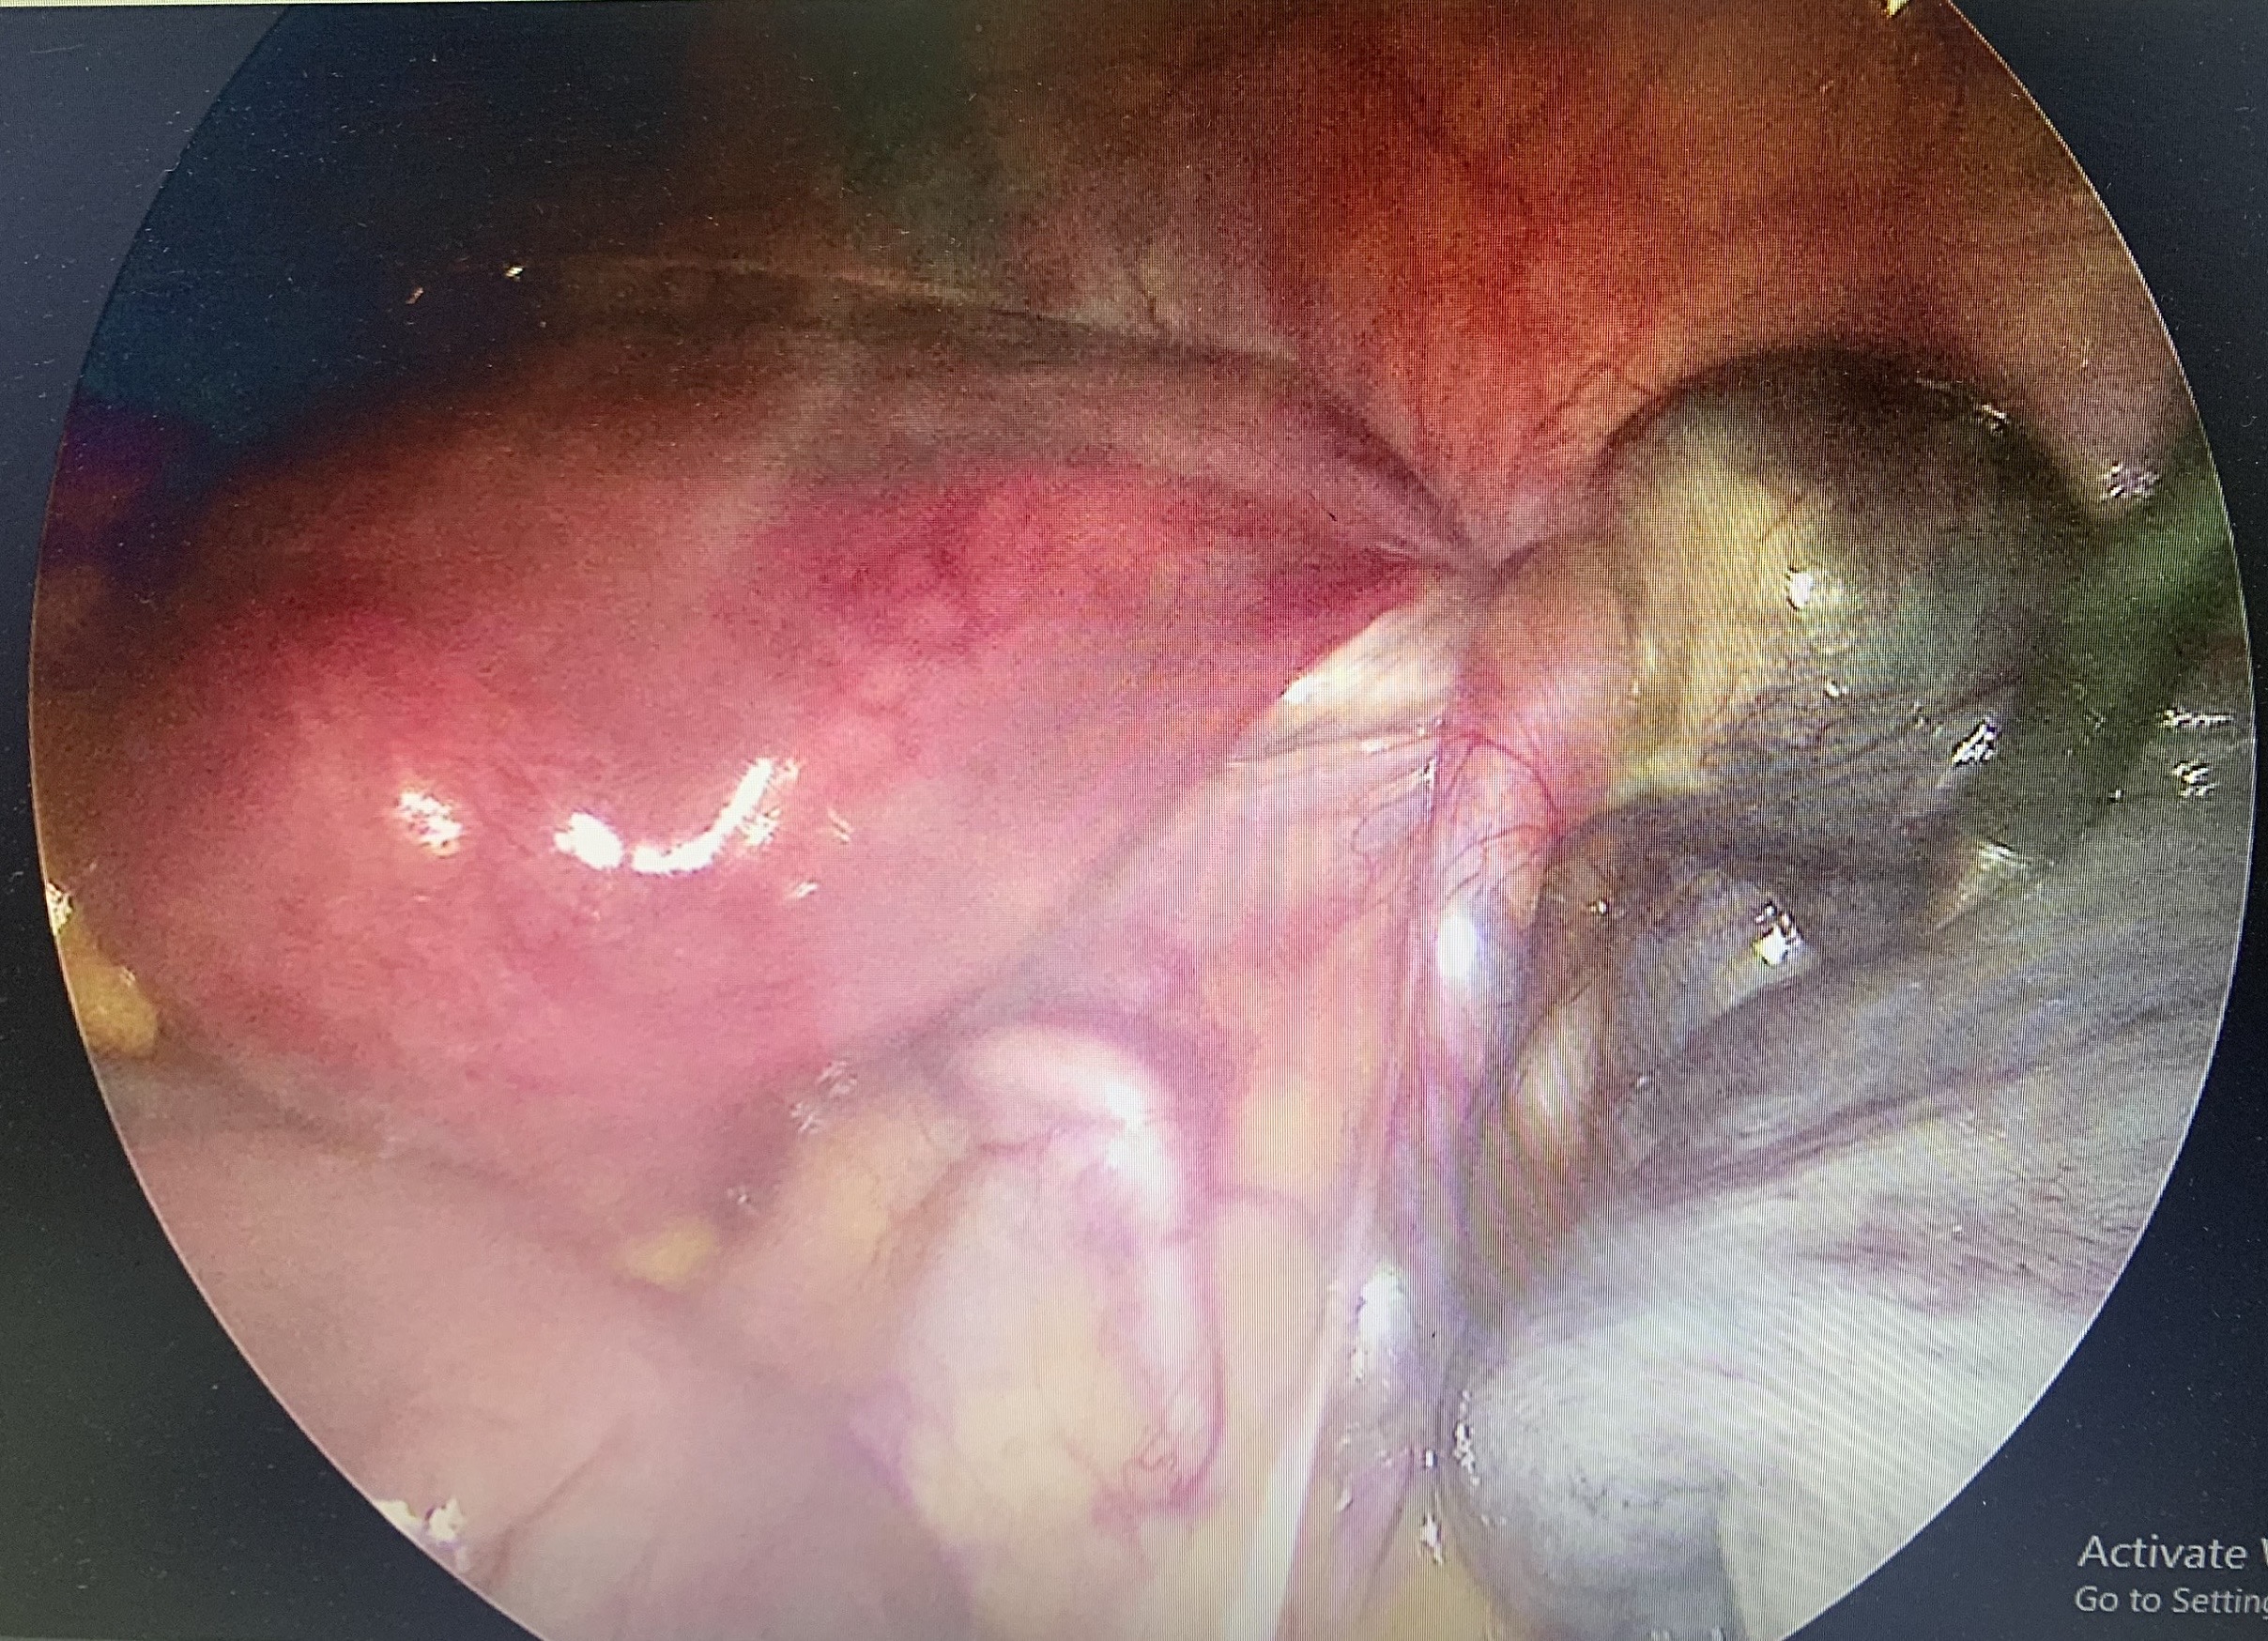

Specialist doctor level 2 Hoang Thi Kim Ngan’s team performing the surgery

The surgery was performed by the team led by Specialist doctor level 2 Hoang Thi Kim Ngan, Head of the Obstetrics and Gynecology Department at Yen Binh General Hospital. After five days of postoperative care, Ms. D’s health stabilized.